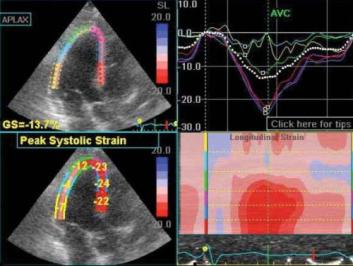

An electric picture is drawn on the large computer, and you can see heart rate, chambers of the heart, blood flows, passages, etc.  It is an impressive piece of equipment.

The sole purpose is to provide your doctor with critical and timely information about how your heart; how it is functioning, the heart beats, blocks and the all famous Ejection Fraction aka EF.

The information obtained from the echocardiogram will help the doctor diagnose and treat your heart disease, and it will confirm if things are working just fine or not.